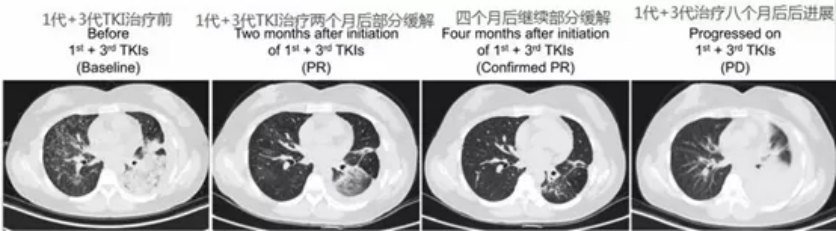

这里列举一例奥希替尼轮换治疗。一女性患者,61岁,晚期肺腺癌伴脑转,L858R阳性,先后使用吉非替尼、厄洛替尼、化疗,阿法替尼治疗了4.2年。患者的右胸膜转移灶测得T790M突变(组织为腺癌),但发现右横膈膜附近的胸膜肿瘤转化成小细胞肺癌。患者使用奥希替尼及化疗(卡铂+伊立替康)轮换治疗,在一处病灶发生进展后立即切换另一方案,具体见下图。